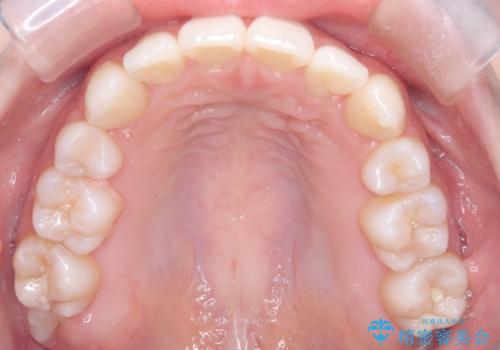

- 左上の犬歯の凸凹や正中のずれを主訴に来院されました。

凸凹を治すために、上下左右の小臼歯を抜歯してワイヤー矯正を行いました。

患者様には、顎間ゴムを使用していただくことで、2年という期間で治療を終了することができました。